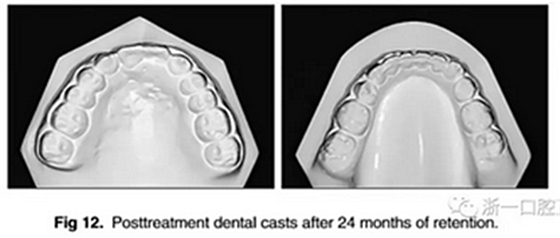

經(jīng)過24個(gè)月的保持后,咬合保持得很好(圖11 ; 圖12)。在上牙弓中,應(yīng)用固定舌側(cè)保持器以防止任何復(fù)發(fā)傾向。在下牙弓中,治療后拔除第三磨牙。